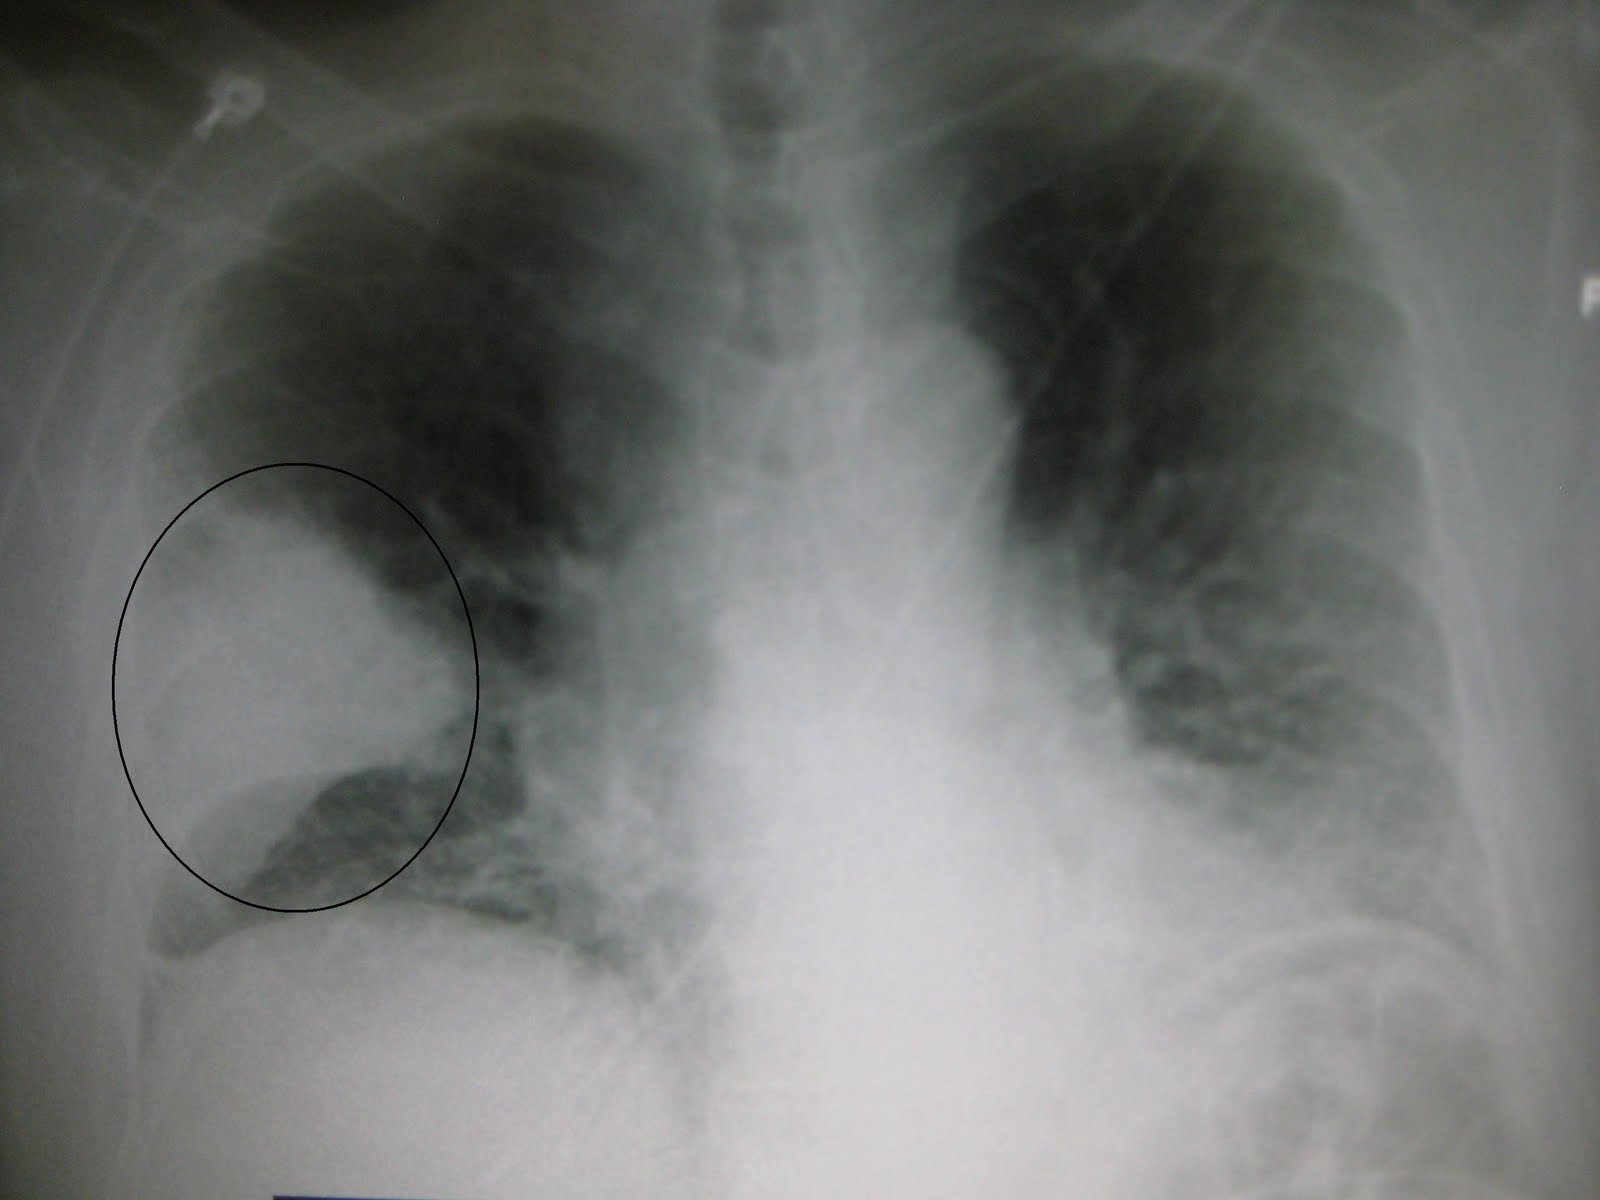

1:威廉●奧斯勒把肺炎叫作「死神隊長」。肺炎是當時世界上的頭號殺手,超過肺結核、癌症、心臟病、和鼠疫。

所謂「當時」是指1918年致命西班牙流感爆發的時期,當年醫學水平遠低於在,亦沒有抗生素可用,致死率相當高,即使現在肺炎仍名列第5或第6的死亡原因,由此可見其對人體的危害性

,有些引起肺炎的病原並非由細菌(如流感及沙士),亦增加了治療的困難,其綽號「死神隊長」並非浪得虛名。